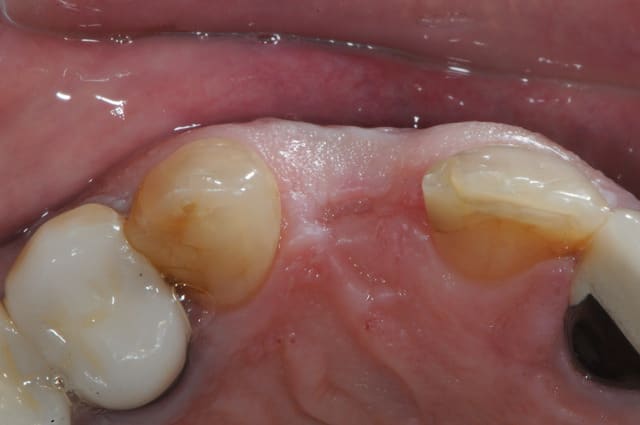

-22:dent foutue

-avulsion au périotome' un p'tit coup à gauche, un ptit coup à droite...)

- la dent avec du beurk au bout

-le site d'extraction

-vérification de l'existence d'une table externe

-implantation (je passe les détails)

- prélèvement d'une petite pièce de gencive libre

- suture de la "pastille" de gencive

-j+10 jours

-+1 mois